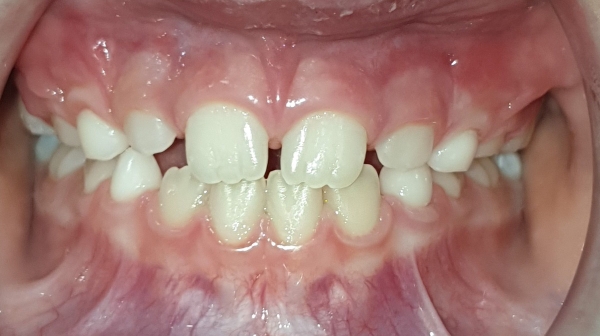

ANTES